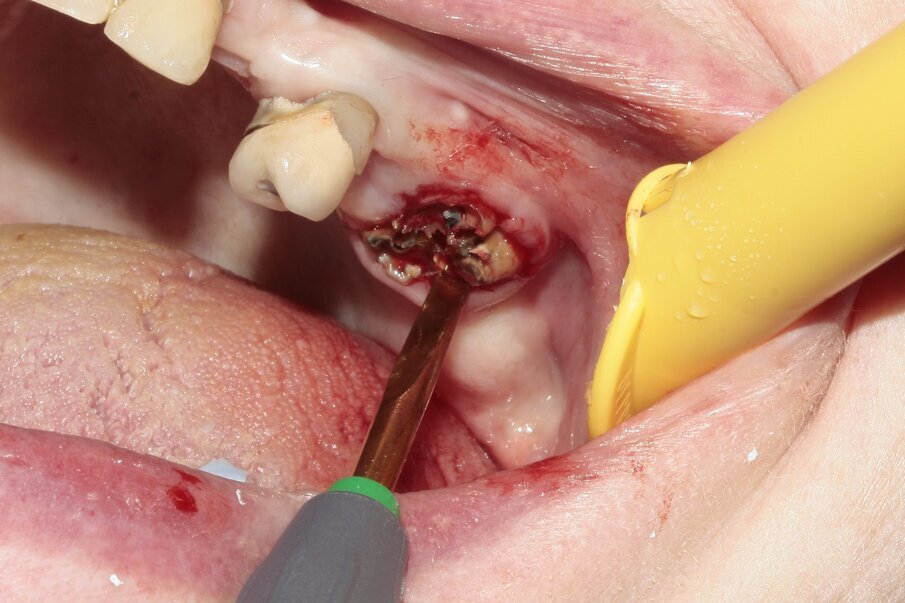

A 75-year-old female patient visited our dental clinic reporting a loose crown on tooth #26. The tooth had been endodontically treated in the past and had a carbon-fibre post. The tooth had been prosthetically restored and presented severe caries without early apical destruction or alteration. The patient had previously had a gold crown on the tooth.

Fig. 1: Tooth #26 presented bent and diverging roots. The tooth was severely decayed.